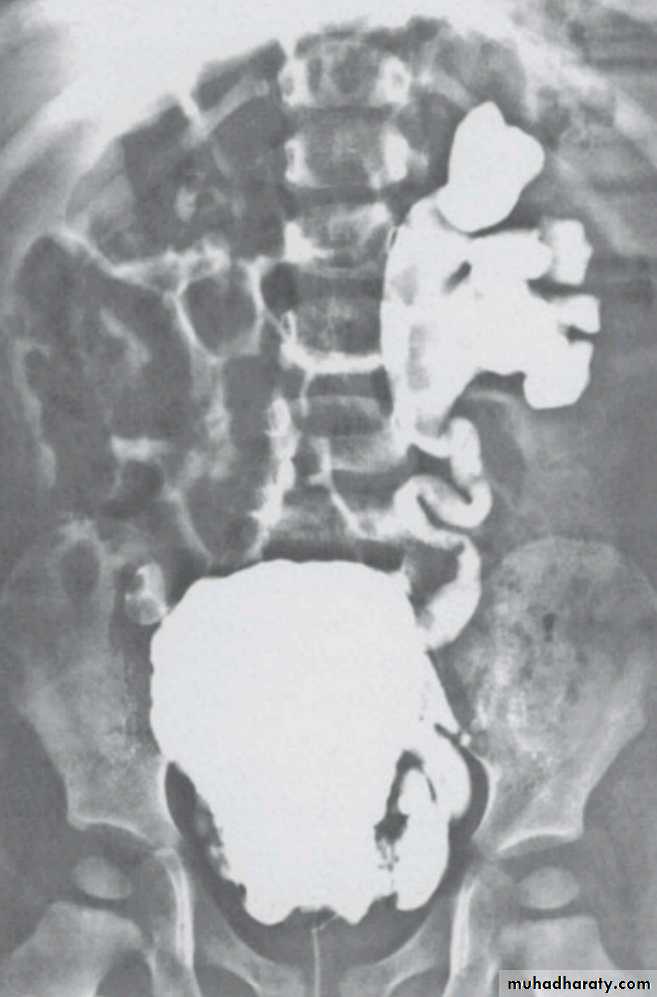

WHAT ARE THE POSSIBLE UNDERLYING CAUSES ?PUJ obstruction

VURPosterior urethral valve ( males only )

PUJ obstruction

U/S : AP diameter of the renal pelvis, kidney size.IVP

CT scanRadionuclide renography : the best radiographic study.

U/SIVP

CT scan

VUR

Voiding cystourethrogram

POSTERIOR URETHRAL VALVE

Voiding cystourethrogram.Excretory urogram.